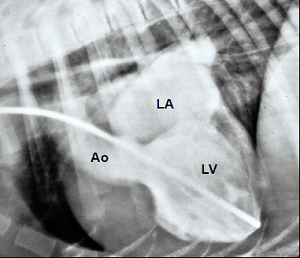

One of the primary calculations which veterinary cardiologists make when gathering data during echocardiographic (echo) scans of dogs' hearts is the LA/Ao ratio (LA ÷ Ao). "LA" stands for the left atrium of the heart, and in this context it is the linear diameter of the left atrium in either millimeters (mm.) or centimeters (cm.). "Ao" stands for the aortic root of the heart, and that is the linear diameter of the aorta artery at its starting point in the left ventricle of the heart, similarly in millimeters or centimeters.

The left atrium (LA) is one of the two chambers of the dog's heart (the

other being the left ventricle) which

enlarge as MVD progresses from just a soft murmur to congestive heart failure

(CHF). If in consecutive echo examinations of the same patient, the

cardiologist finds that the diameter of the LA has increased significantly,

that indicates that the MVD has progressed and the need to medicate the dog

with pimobendan. So, comparing the diameter of the LA in consecutive echo

scans is extremely important information in terms of treating the patient.

However, the aortic root (Ao) of the heart plays no role whatsoever in the progression of MVD. And, most significantly, the diameter of the Ao is not a constant number. It can change so that in one echo scan the Ao's diameter can be x and in a later scan it can be y. Indeed, the condition of the aortic root has been known to change as the dog ages; it deteriorates. So, the size of the Ao when measured when the dog is 5 years old may not be the same as it is when the same dog is examined at age 6 years. In short, it makes no sense to include the Ao measurement in calculations of changes in the dimension of the LA of a single dog.

A dilemma which veterinary cardiologists face when performing an initial echo scan of the heart of a MVD-affected dog is how to determine upon that initial scan whether the LA still is of normal size or already has begun to enlarge. Researchers attempt to resolve that difficulty by predicting the size of normal-sized LAs. The LA/Ao ratio was devised by medical researchers in a 1974 study of humans, based upon the assumption that humans' normal sized LAs and Aos are proportional to each other, and so the LA/Ao ratio can indicate a reference range of normal sized human left atriums and degrees of left atrial enlargement. If a patient's heart had never been echo scanned prior to suspected left atrial enlargement, the LA/Ao reference range can be used as a best guess as to whether any enlargement already has occurred.

That said, the LA/Ao clearly has no useful role whatsoever when examining only a single dog's heart to determine if that dog's LA has enlarged between two consecutive echo exams. Since the Ao's diameter can be different in different echo scans of the same dog, when the Ao is included in an effort to determine if only the LA has increased in size, the result completely falsifies the diagnosis. Only if the Ao diameter is constant for all echo scans of that dog -- a very unlikely event -- will the LA/Ao ratio provide any useful information about the size of the dog's LA.